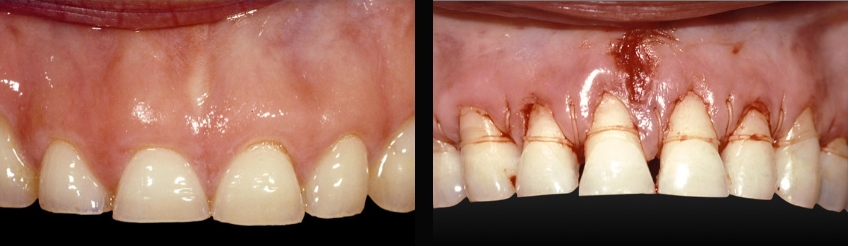

Your discussion should highlight the fact that as wear progresses, it will spread to more and more teeth in the mouth, making the potential treatment far more complex and expensive. It is also important to acknowledge that as tooth wear progresses, the teeth will often move — erupt, if you will — from dentoalveolar extrusion to maintain occlusal contact. This means the teeth are getting shorter and shorter and future treatment may involve possible crown lengthening to reposition gingiva and bone to expose more tooth (Figs. 1–5). If crown lengthening is necessary for a patient, Spear members can use the patient education video Crown Lengthening (Tooth Wear), which illustrates this well.

Examples of treatment options may be crown lengthening vs. intrusion to reposition overerupted anterior teeth (Figs. 6–10). You can explain each — or show the Spear Patient Education videos of each — then discuss with the patient why you believe one may be better for them.